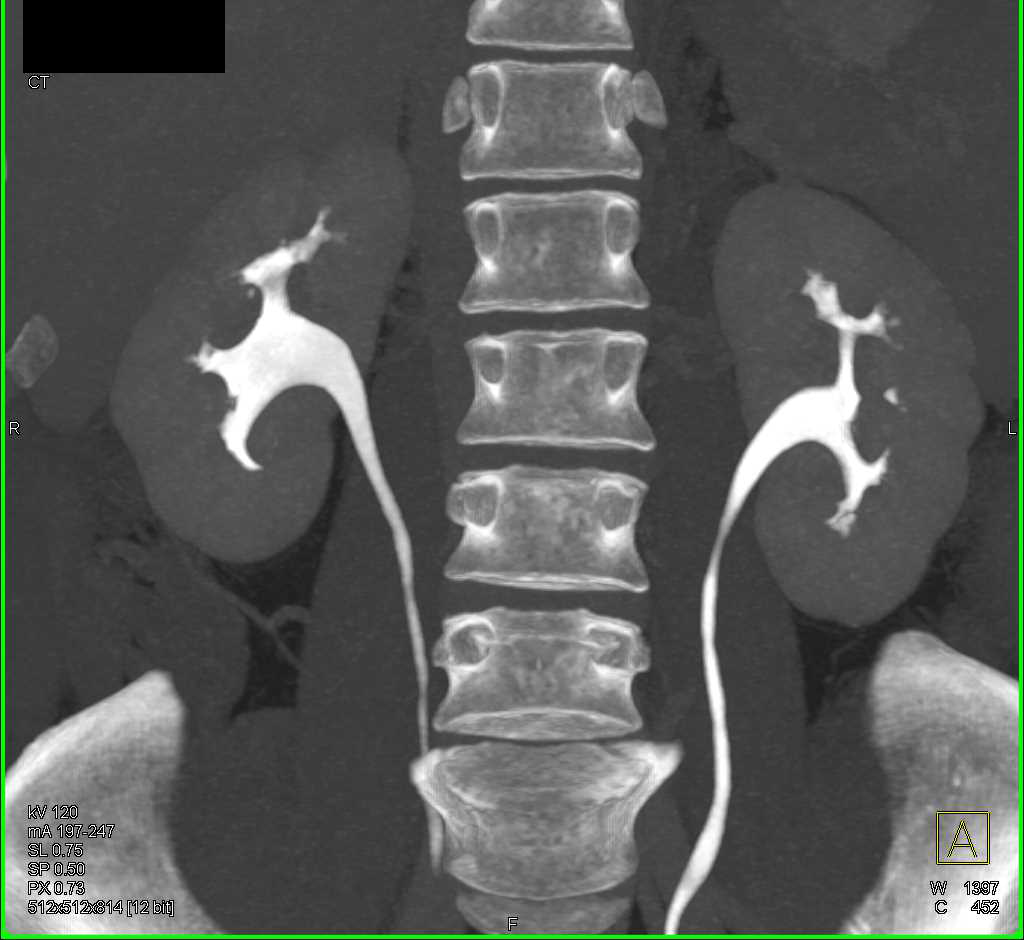

Large Bladder Stone Forms Around a Catheter that had been in Place for Years